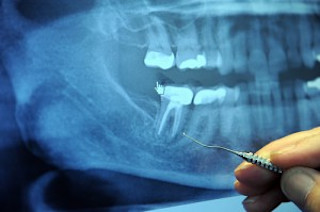

"Health care depends, in part, on the ability of a practitioner to see signs of disease and to see how to treat it. Visual illusions, therefore, could affect health care. Yet there is very little prospective evidence that illusions can influence treatment. We sought such evidence. METHODS AND RESULTS: We simulated treatment using dentistry as a model system. We supplied eight, practicing, specialist dentists, endodontists, with at least 21 isolated teeth each, randomly sampled from a much larger sample of teeth they were likely to encounter. Teeth contained holes and we asked the endodontists to cut cavities in preparation for filling. Each tooth presented a more or less potent version of a visual illusion of size, the Delboeuf illusion, that made the holes appear smaller than they were. Endodontists and the persons measuring the cavities were blind to the parameters of the illusion. We found that the size of cavity endodontists made was linearly related to the potency of the Delboeuf illusion (p<.01) with an effect size (Cohen's d) of 1.41. When the illusion made the holes appear smaller, the endodontists made cavities larger than needed. CONCLUSIONS: The visual context in which treatment takes place can influence the treatment. Undesirable effects of visual illusions could be counteracted by a health practitioner's being aware of them and by using measurement."

Example of the Delboeuf Illusion Related content: Seriously, Science?: A new thing to fear: “intranasal teeth”. NCBI ROFL: Snakes vs. dentist: pick your poison. NCBI ROFL: No way. According to my tongue, that hole is definitely wider. (That's what she said.)